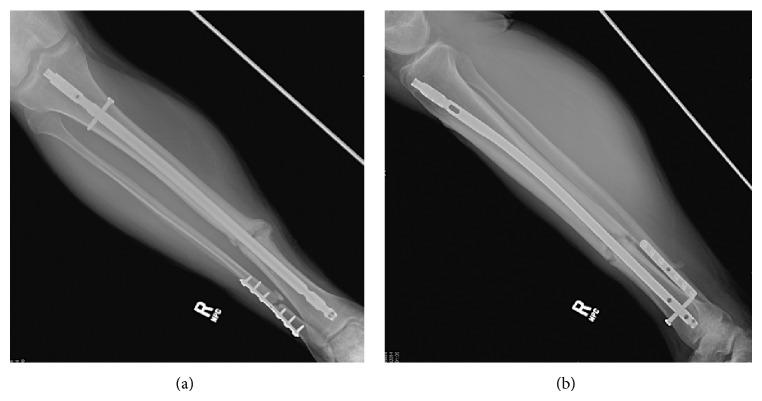

Determining whether a bone fracture is healed is one of the most important and fundamental clinical determinations made in orthopaedics. However, there are currently no standardized methods of assessing fracture union, which in turn has created significant disagreement among orthopaedic surgeons in both clinical and research settings. An extensive amount of research has been dedicated to finding novel and reliable ways of determining healing with some promising results. Recent advancements in imaging techniques and introduction of new radiographic scores have helped decrease the amount of disagreement on this topic among physicians. The knowledge gained from biomechanical studies of bone healing has helped us refine our tools and create more efficient and practical research instruments. Additionally, a deeper understanding of the molecular pathways involved in the bone healing process has led to emergence of serologic markers as possible candidates in assessment of fracture union. In addition to our current physician centered methods, patient-centered approaches assessing quality of life and function are gaining popularity in assessment of fracture union. Despite these advances, assessment of union remains an imperfect practice in the clinical setting. Therefore, clinicians need to draw on multiple modalities that directly and indirectly measure or correlate with bone healing when counseling patients.